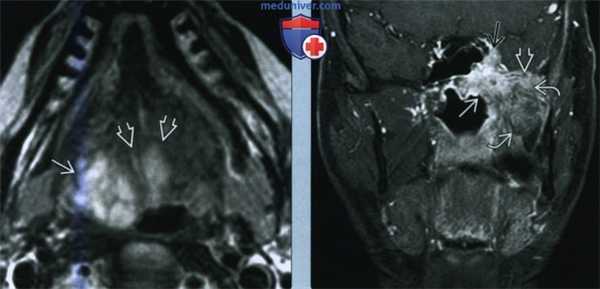

(Слева) MPT Т2ВИ FS в аксиальной проекции. В обеих небных миндалинах определяются мультифокальные лимфомы. Четкие края опухолей говорят о том, что они находятся в пределах капсул миндалин.

(Справа) MPT Т1ВИ FS с КУ, аксиальная проекция, этот же пациент. Определяется участок лимфомы в области лимфоидной ткани корня языка слева и крупный некротизированный лимфоузел IB уровня. На шее также визуализируются несколько мелких лимфоузлов, но установить, поражены ли они лимфомой, можно только при помощи метаболических исследований, например, ПЭТ/КТ.